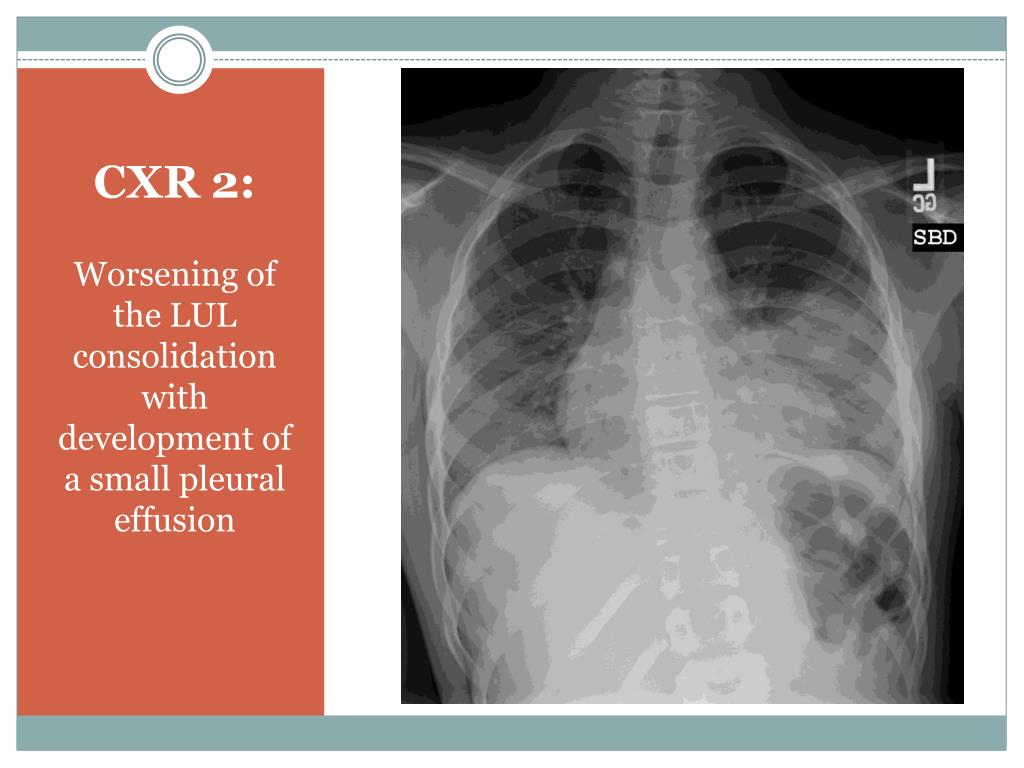

Understanding Acute Chest Syndrome in Sickle Cell Disease: Diagnosis and Management

5. CXR 2: Worsening of the LUL consolidation with development of a small pleural effusion

10. ACS Clinical Manifestations • Fever, cough, chest pain = most common • SOB, wheeze, hemoptysis, chills • Hypoxia and respiratory distress • New infiltrate on CXR • Upper lobe more common in children • Can be multi-lobar • Associated pleural effusion • Hgb decreased from baseline • Leukocytosis • + blood cultures and/or sputum or BAL cultures